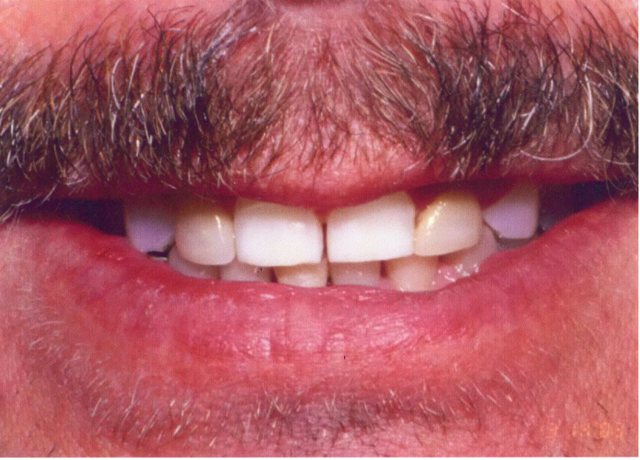

Περιστατικό 1 | Περιστατικό 2 | Περιστατικό 3 |

Περιστατικό 1 | Περιστατικό 2 |

Περιστατικό 1 | Περιστατικό 2 | Περιστατικό 3 |

Περιστατικό 1 | Περιστατικό 2 |

Περιστατικό 1 | Περιστατικό 2 |